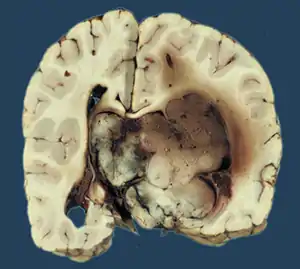

Choroid plexus tumors are divided into three categories by the World Health Organization (2016):[9] papillomas (grade I), atypical tumors (grade II), and carcinomas (grade III). Less than two mitotic figures per 10 high power fields are present in CPPs, two to five are present in atypical ones, and more than five are present in carcinomas. The tumors are visible as pink, soft, spherical lumps with erratic projections and considerable vascularity.

The tumor is neuroectodermal in origin and similar in structure to a normal choroid plexus. They may be created by epithelial cells of the choroid plexus. Papillary fronds lined by bland columnar epithelium are visible under the microscope. Normal absences include mitotic activity, nuclear pleomorphism, and necrosis.[10] Tumors have positive immunohistochemistry for cytokeratin, vimentin, podoplanin, and S-100.[11] Up to 20% of choroid plexus papilloma patients may test positive for glial fibrillary acidic protein (GFAP).[12] Studies have found that fourth ventricle cancers express more S100 than lateral ventricle tumors, and older patients (over 20 years) express more GFAP and transthyretin than younger patients.[13] Some individuals with choroid plexus papilloma have germline TP53 gene mutations, according to genetic analyses.[14] These cancers rarely exhibit nuclear p53 protein positivity. Aicardi syndrome, hypomelanosis of Ito, and 9p duplication are syndromic correlations of choroid plexus papilloma.

Micrograph of a choroid plexus papilloma. H&E stain.